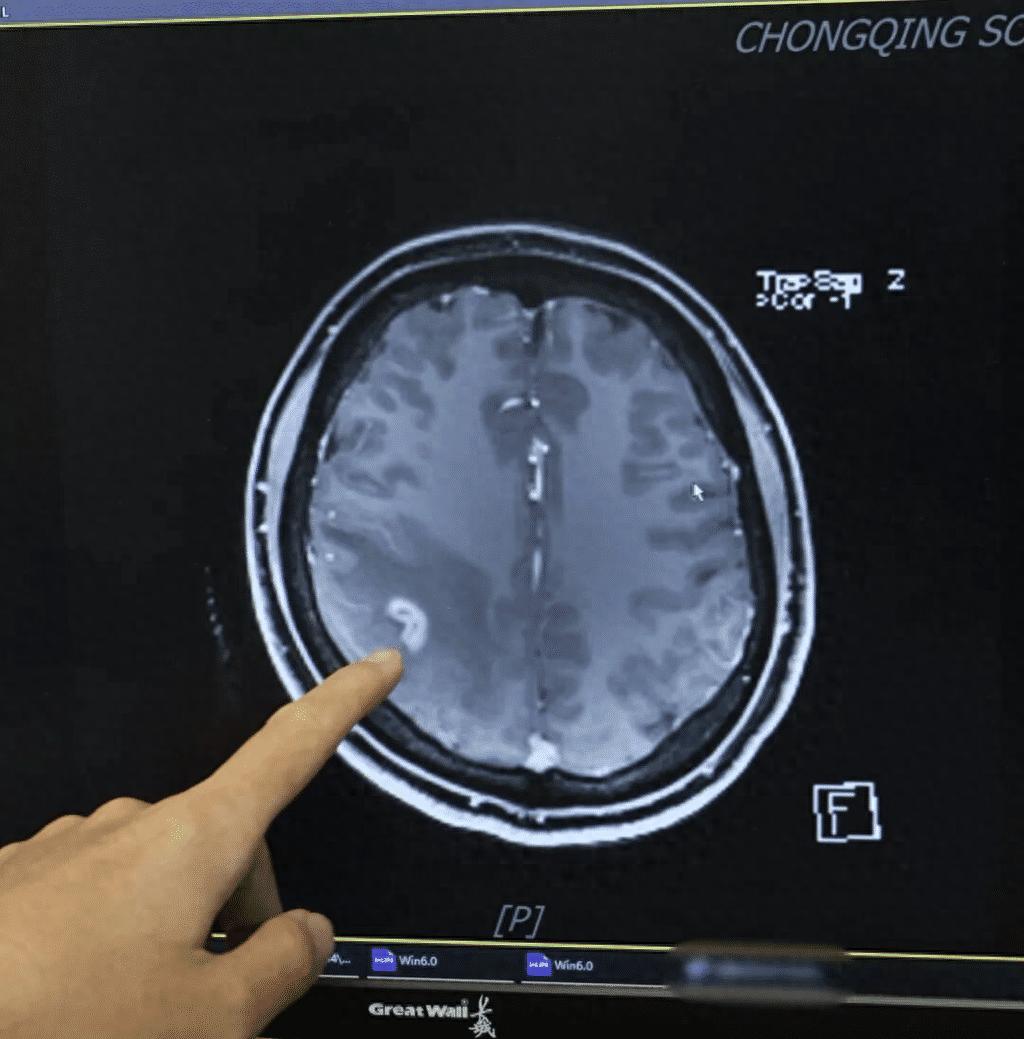

• 女子多年肢体麻木开颅抓出3厘米活虫!

女子多年肢体麻木开颅抓出3厘米活虫!“太感谢了,这么多年终于找到了病因!”3月26日,记者从陆军军医大学西南医院获悉,该院神经内科日前收到了一面来自患者的锦旗,感谢团队帮助她治好了脑部寄生虫感染。患者王女士回忆(化名),5年前她先是突然出现...